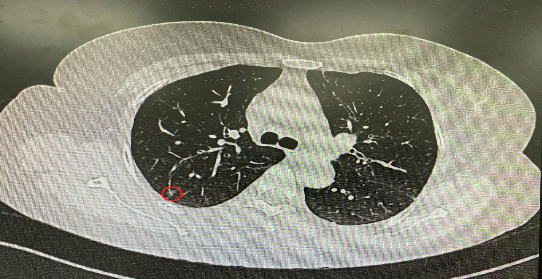

今年54歲的李女士(化名)7月初突然出現(xiàn)右上部腹痛,起初并未在意,以為稍作休息就會好轉(zhuǎn),但疼痛卻并未消退,持續(xù)了一個星期。李女士實在難以忍受,才在家人陪伴下來到西安國際醫(yī)學(xué)中心醫(yī)院就診。胸外科二病區(qū)崔凱主任接診患者后,詳細詢問病情并查閱檢查資料,經(jīng)胸部HRCT檢查,結(jié)果提示:右肺上葉后段混合密度結(jié)節(jié)影,考慮原位癌可能,即將患者收入胸腔外科二病區(qū)住院治療。

經(jīng)與患者家屬溝通,崔凱主任決定行外科手術(shù)治療。為達到精準切除,術(shù)前需進行肺小結(jié)節(jié)切除前定位。由于結(jié)節(jié)位于右肺上葉后段,傳統(tǒng)經(jīng)胸外穿刺術(shù)無法抵達病灶。崔凱主任與呼吸內(nèi)科一病區(qū)歐陽海峰主任討論后,決定擬行LungPro全肺診療導(dǎo)航下染色定位。即術(shù)前通過Lung Pro導(dǎo)航規(guī)劃染色位置,經(jīng)Lung Pro實時引導(dǎo)支氣管鏡抵達既定位置,注入亞甲藍染色劑標記結(jié)節(jié)位置。

使用術(shù)前規(guī)劃系統(tǒng)重建全肺3D模型,并于外科醫(yī)生討論染色位置,最終確定標記染色點—右肺上葉后段b亞段(RB2b)。術(shù)中使用P290(4.9mm外徑)標準支氣管鏡,根據(jù)導(dǎo)航術(shù)前規(guī)劃路徑,Lung Pro實時導(dǎo)航下,GS鞘管進入RB2b遠端官腔外病灶并注射亞甲藍染色劑。

一切準備就緒,7月15日,崔凱主任團隊聯(lián)合歐陽海峰主任團隊為患者行單孔胸腔鏡下右肺上葉后段切除術(shù),手術(shù)用時128分鐘順利完成。進入胸腔后,亞甲藍染色部位明顯,患者發(fā)生癌變的右肺上葉后段被成功切除。術(shù)后標本根據(jù)染色部位迅速找到結(jié)節(jié),剖開位置兼染色位置和病灶完全符合,行術(shù)中冰凍后快速送病理檢查。經(jīng)術(shù)后病理檢查,明確診斷為(右肺上葉)原位腺癌。